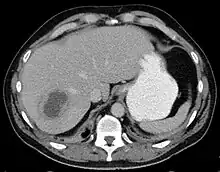

Liver abscess on axial CT image: a hypodense lesion in the liver with peripherally enhancement. | |